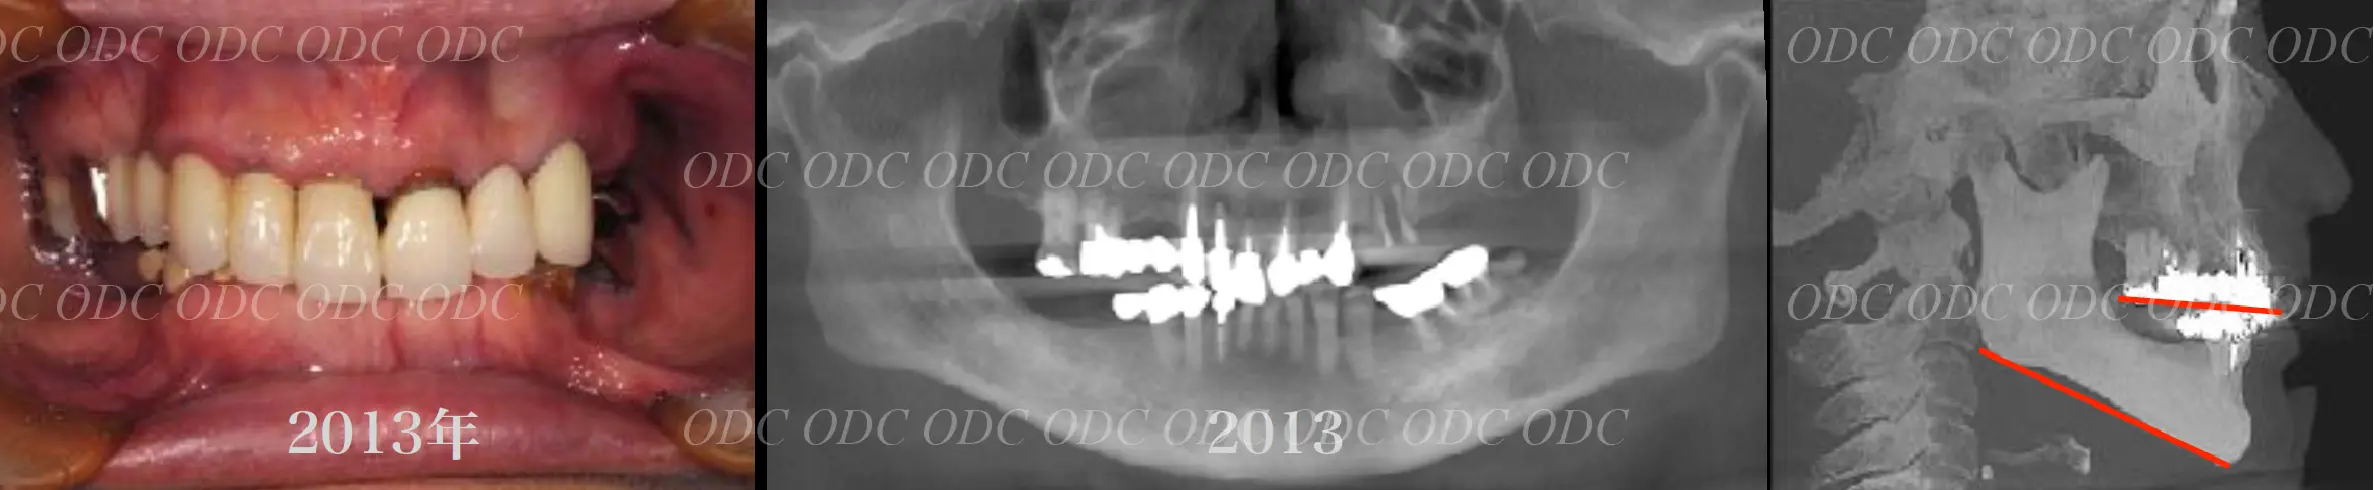

2011年、噛めないという主訴で65歳の男性が来院されました。

全顎的な治療を希望されていましたので、口腔内はもちろん骨格・顔貌・顎関節の診断を行い治療目標を設定致しました。

上顎天然歯に関しては矯正治療、下顎にはフルマウスのインプラント治療を計画致しました。

顎関節の安定を確認した後、矯正治療とインプラント治療を並行して行いました。

約3年の治療期間を経て、計画通りの満足のいく結果を獲得することができました。

2014年、治療終了時の口腔内の状態です。

インプラント上部構造はCADCAMによって作成されたジルコニアの上部構造です。

2024年、治療終了後約10年が経過いたしました。

顎関節を考慮した包括的な治療を行うことで咬合状態(噛み合わせ)は現在もとても安定した状態です。